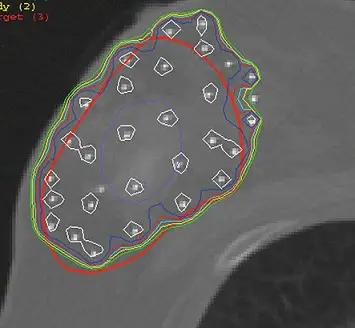

下圖為何種放射治療之治療計畫?

- 解剖構造辨識:影像顯示為人體的電腦斷層(CT)橫斷面。可觀察到表面向外突出的軟組織(乳房),以及下方呈現低密度的區域(肺部)與骨骼結構(肋骨)。由此可明確判定解剖位置為胸壁與乳房。

- 射源與劑量分布特徵:

- 影像中可見散佈於特定區域(紅色線條圈選處,代表臨床標靶體積 CTV 或 PTV,通常為腫瘤切除後的空腔及邊緣)內的多個「白色高密度亮點」。這些亮點代表**組織間插種(Interstitial implants)**所植入的導管(Catheters)或治療針。

- 等劑量曲線(Isodose curves,圖中藍、綠、黃等線條)緊密且順形地環繞在這些導管周圍,呈現近接治療典型的「高劑量梯度(High dose gradient)」特性,亦即劑量在射源附近極高,但隨距離增加而快速衰減,有效保護了深層的胸壁與肺臟組織。

- 綜合判斷:此為典型的**多導管組織間乳房近接治療(Multicatheter interstitial breast brachytherapy)